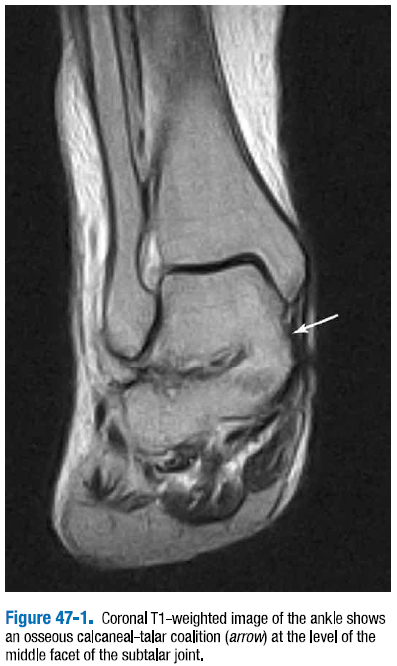

족근 결합의 이차적 징후는 거골 부리모양(talar beaking)과 구상발목관절(ball-and-socket ankle joint)이다. 골성 결합의 MRI 진단은 골수의 연속성에 의해 나타나는데, 복잡하지 않다.(그림 47-1) 섬유연골성이나 섬유골성은 불규칙성과 낮은 신호의 섬유조직의 띠의 관절 표편 평가가 요구되는데, 이는 판별하기 좀 더 어렵다.

△ 그림 47-1. 발목의 관상면 T1 강조영상

거골하관절의 중앙관절면 레벨에서 골성 종골-거골 결합(화살표)을 보여준다.